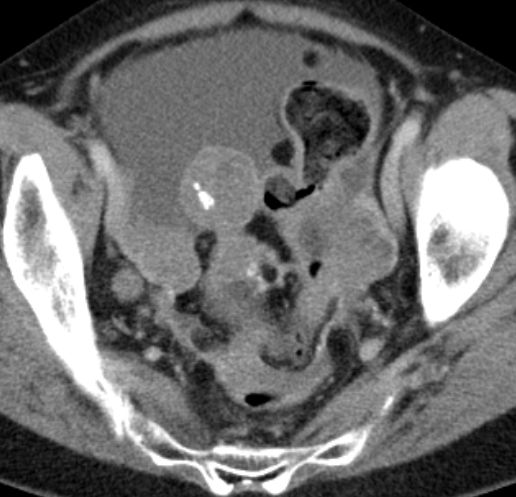

Ascites bei Ovarial - Ca |

Pleuraerguß links bei Ovarial - Ca |

Fortgeschrittenes Ovarialkarzinom mit Ascites und Peritonealkarzinose.![]() | ||